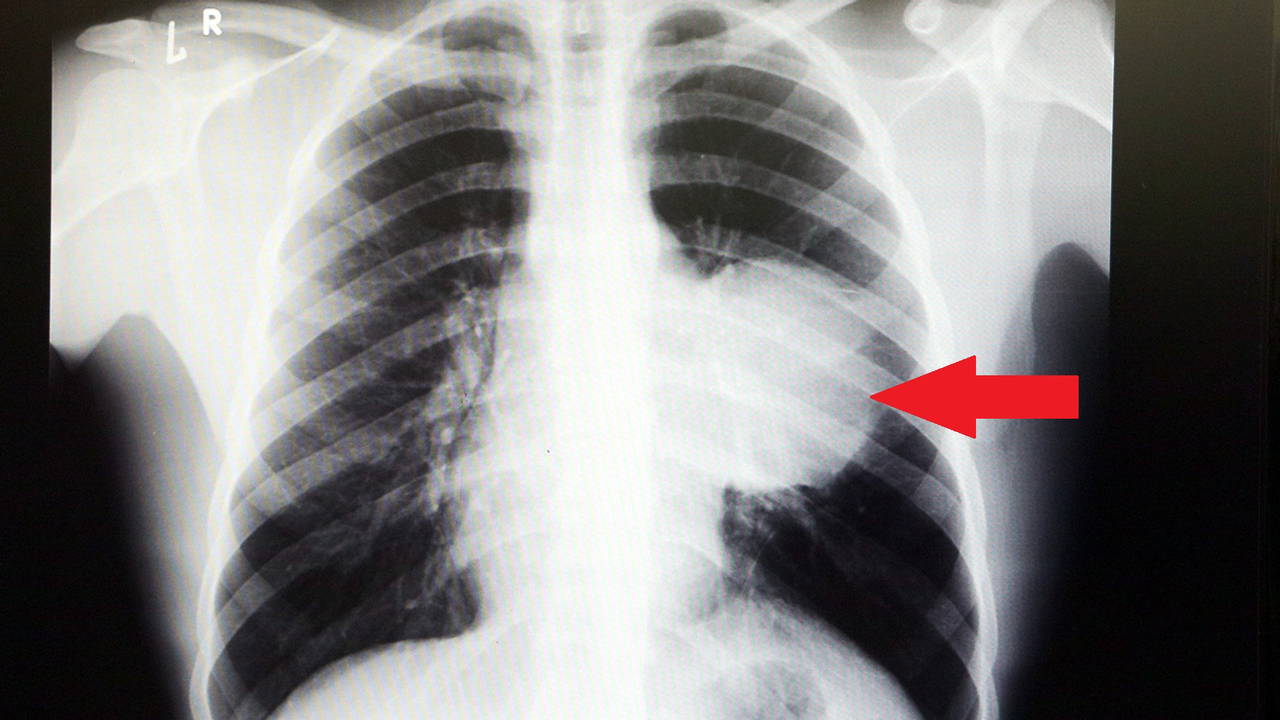

Her şey yolundaydı ve raporunu alarak iş başı yaptı. Bir ay geçmeden nefes darlığı, halsizlik, öksürük gibi şikayetlerle başka bir hastaneye gittiğinde ise ilk şoku yaşadı. Sol göğüs boşluğunda portakal büyüklüğünde bir kitle tespit edildi. Yapılan biyopside tümörün akciğer kaynaklı olmadığı, henüz cenin aşamasında eşey hücrelerinin farklılaşmasıyla gelişen "immatür teratom" teşhisi kondu.

"Bu nedenle vücuduna yeterince kan gitmiyordu. Ağustos ayının başında portakal büyüklüğündeyken kitle Eylül sonuna irice bir kavun, Ekim ayına geldiğimizde ise bir karpuz büyüklüğüne ulaştığı için, kitlenin büyüme hızı bizi acilen ameliyat yapmaya yöneltti. Yaklaşık 8-10 kat hacimsel olarak artmıştı. Sol akciğer tamamen ezilmiş ve kağıt haldeydi, alt lobu anestezi ekibimiz yüksek basınç uygulayarak tekrar şişirdi. Çok fazla vaktimiz yoktu, kitle basısından dolayı yaşamla bağdaşmayacağından dolayı hızlı hareket etmek zorundaydık. Bize geldikten üç gün sonra hemen ameliyata aldık çünkü tümörden ziyade onun yaptığı baskıdan kaynaklı hayati riski vardı."

"Ama bu hastada yaklaşık 12-13 s santimlik kalbin alt ucununu yer değiştirmesi ve kalbe giren çıkan bütün damarlar bükülüp kan akımı bozulmuştu. Kalp Damar Cerrahisi ekibi de bizimle beraber ameliyata girdi. Sol akciğerin üst lobu artık geri dönüşümsüz olarak ezildiği için çıkarmak zorunda kaldık. Kalbi tekrar eski pozisyonuna getirdik. Ameliyat sonrası çok çabuk toparladı. Koşuyolu ailesi olarak böyle büyük bir vakanın altından başarıyla çıktığımız için de ayrıca çok gururluyuz. Bundan sonra onkolog arkadaşlarımız hastamızın yaşamına çok olumlu dokunuşlar yapacak. İmmatür teratom genelde embriyojenik çağda gelişim gösteren germ hücrelerinin farklılaşmasıyla büyür. Vücudun herhangi bir yerinde gelişebilir ve içinde saç, diş, kemik artıkları, jölemsi kıvamda maddeler bulundurabilen bir tümör çeşididir. Kombine tedavilerde çok iyi sonuçlar alınıyor. Bu çocuğumuzu ileride güzel bir hayat bekliyor."